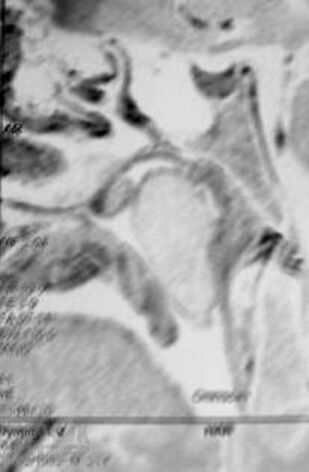

Хронический риносинусит

Представлены данные об этиологии, патогенезе, классификации форм хронического синусита. Приведен обзор современных методов диагностики и лечения. Обсуждается консервативное лечение синуситов с учетом особенностей микрофлоры, освещены не только стандартные хирургические подходы, но и некоторые базовые и прикладные вопросы функциональной эндоскопической риносинусохирургии.